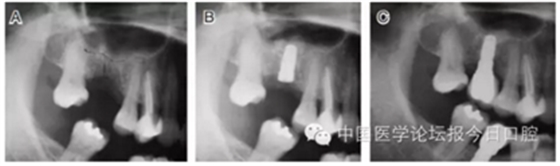

病例4 植入骨替代材料(圖6)

圖6